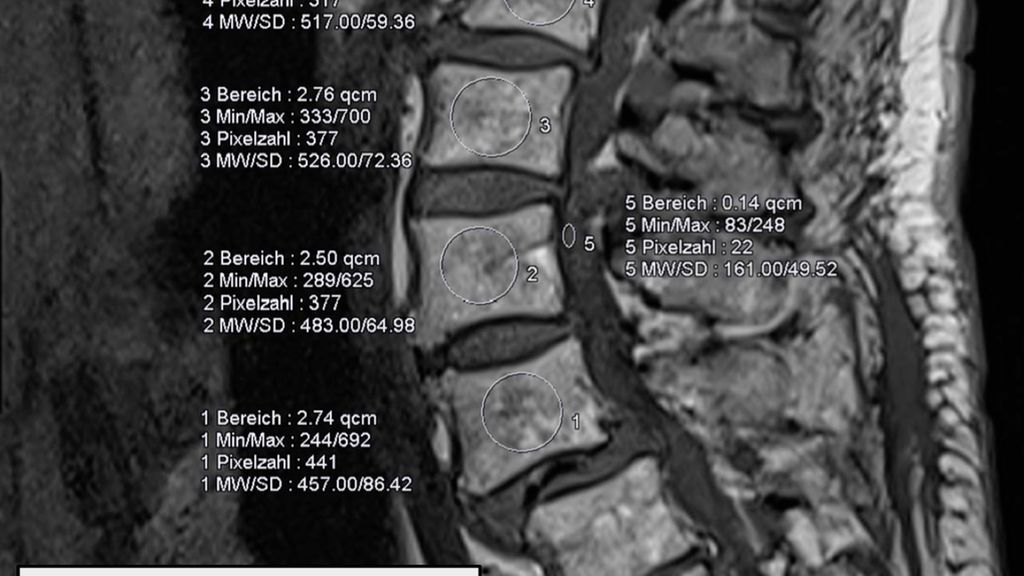

Lässt sich ein Assessment präoperativ zeit- oder strukturbedingt nicht durchführen, können jedoch bereits vorliegende bildgebende Befunde als Informationsquelle genutzt werden. Ein Beispiel ist der MRT-basierte Vertebral Bone Quality Score (VBQ), der im Jahr 2021 von Ehresman et al. beschrieben wurde.9 Die Ermittlung des Wertes wird in Abb. 1 erläutert. Ein anderes Beispiel stellt die Bestimmung der Hounsfield Units (CT-HU) aus einem CT-Scan dar. Ein eindeutiger Cut-off-Wert für den VBQ-Score liegt noch nicht vor, rezente Daten legen jedoch eine Grenze bei ca. 2,4 nahe.10Grundsätzlich besteht eine gute Inter-Rater-Variabilität und die Korrelation mit DEXA-Werten ist gegeben, jedoch kann der VBQ-Score keine DEXA-Messung ersetzen.11 Im Alltag stellt er allerdings eine einfache Möglichkeit dar, Informationen zur Knochendichte zu erlangen, wenn keine rezente DEXA-Messung vorliegt.

Abb. 1: Ermittlung des MRT-basierten Vertebral Bone Quality Score (VBQ) nach Ehresman J et al.9